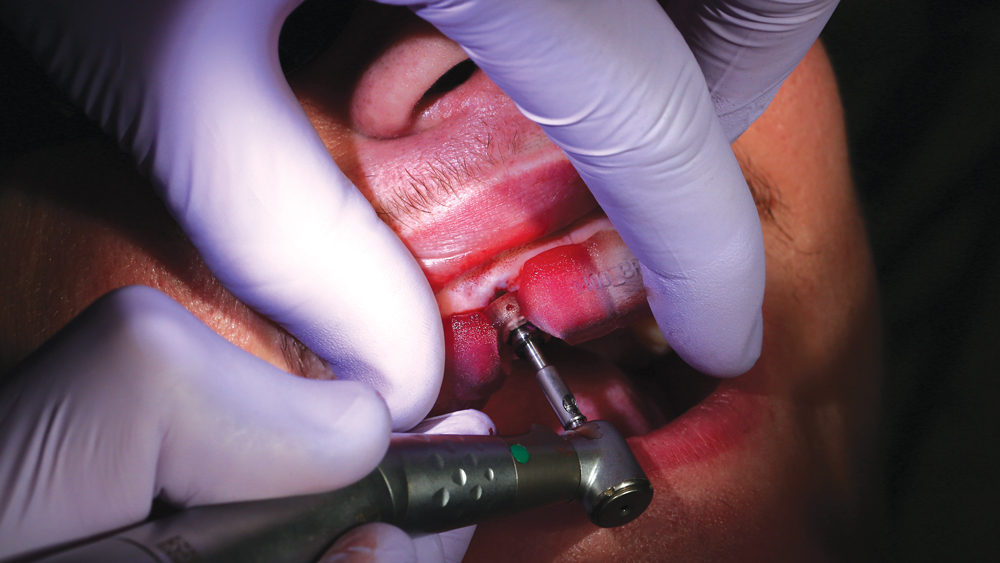

The Hahn Guided Surgical Kit (Glidewell Direct) has been designed to eliminate the need for drill keys, inserts or “spoons” commonly found in other guided surgery systems. The surgical kit’s efficient, straightforward sequence of drills creates an osteotomy in the exact shape, diameter and length of the prescribed implant, ensuring the implant ends up in the exact position determined by the digital treatment plan. Further, the entire surgical procedure, from the initial osteotomy to implant placement, is performed through the surgical guide. Whether using the Digital Treatment Planning service of Glidewell Laboratories or another source for surgical guides, specific guide sleeves are provided to enable practitioners to perform the entire surgical procedure with an efficient and fully guided protocol.

The following case illustrates the efficient, straightforward clinical workflow for placing Hahn Tapered Implants via guided surgery. A digital treatment plan is developed in which a 3.5 mm implant is positioned to support the ideal prosthetic outcome. An immediate provisional crown is designed in concert with the surgical guide and delivered at the time of surgery, helping to produce a predictable, highly esthetic restoration for a demanding case in the smile zone.